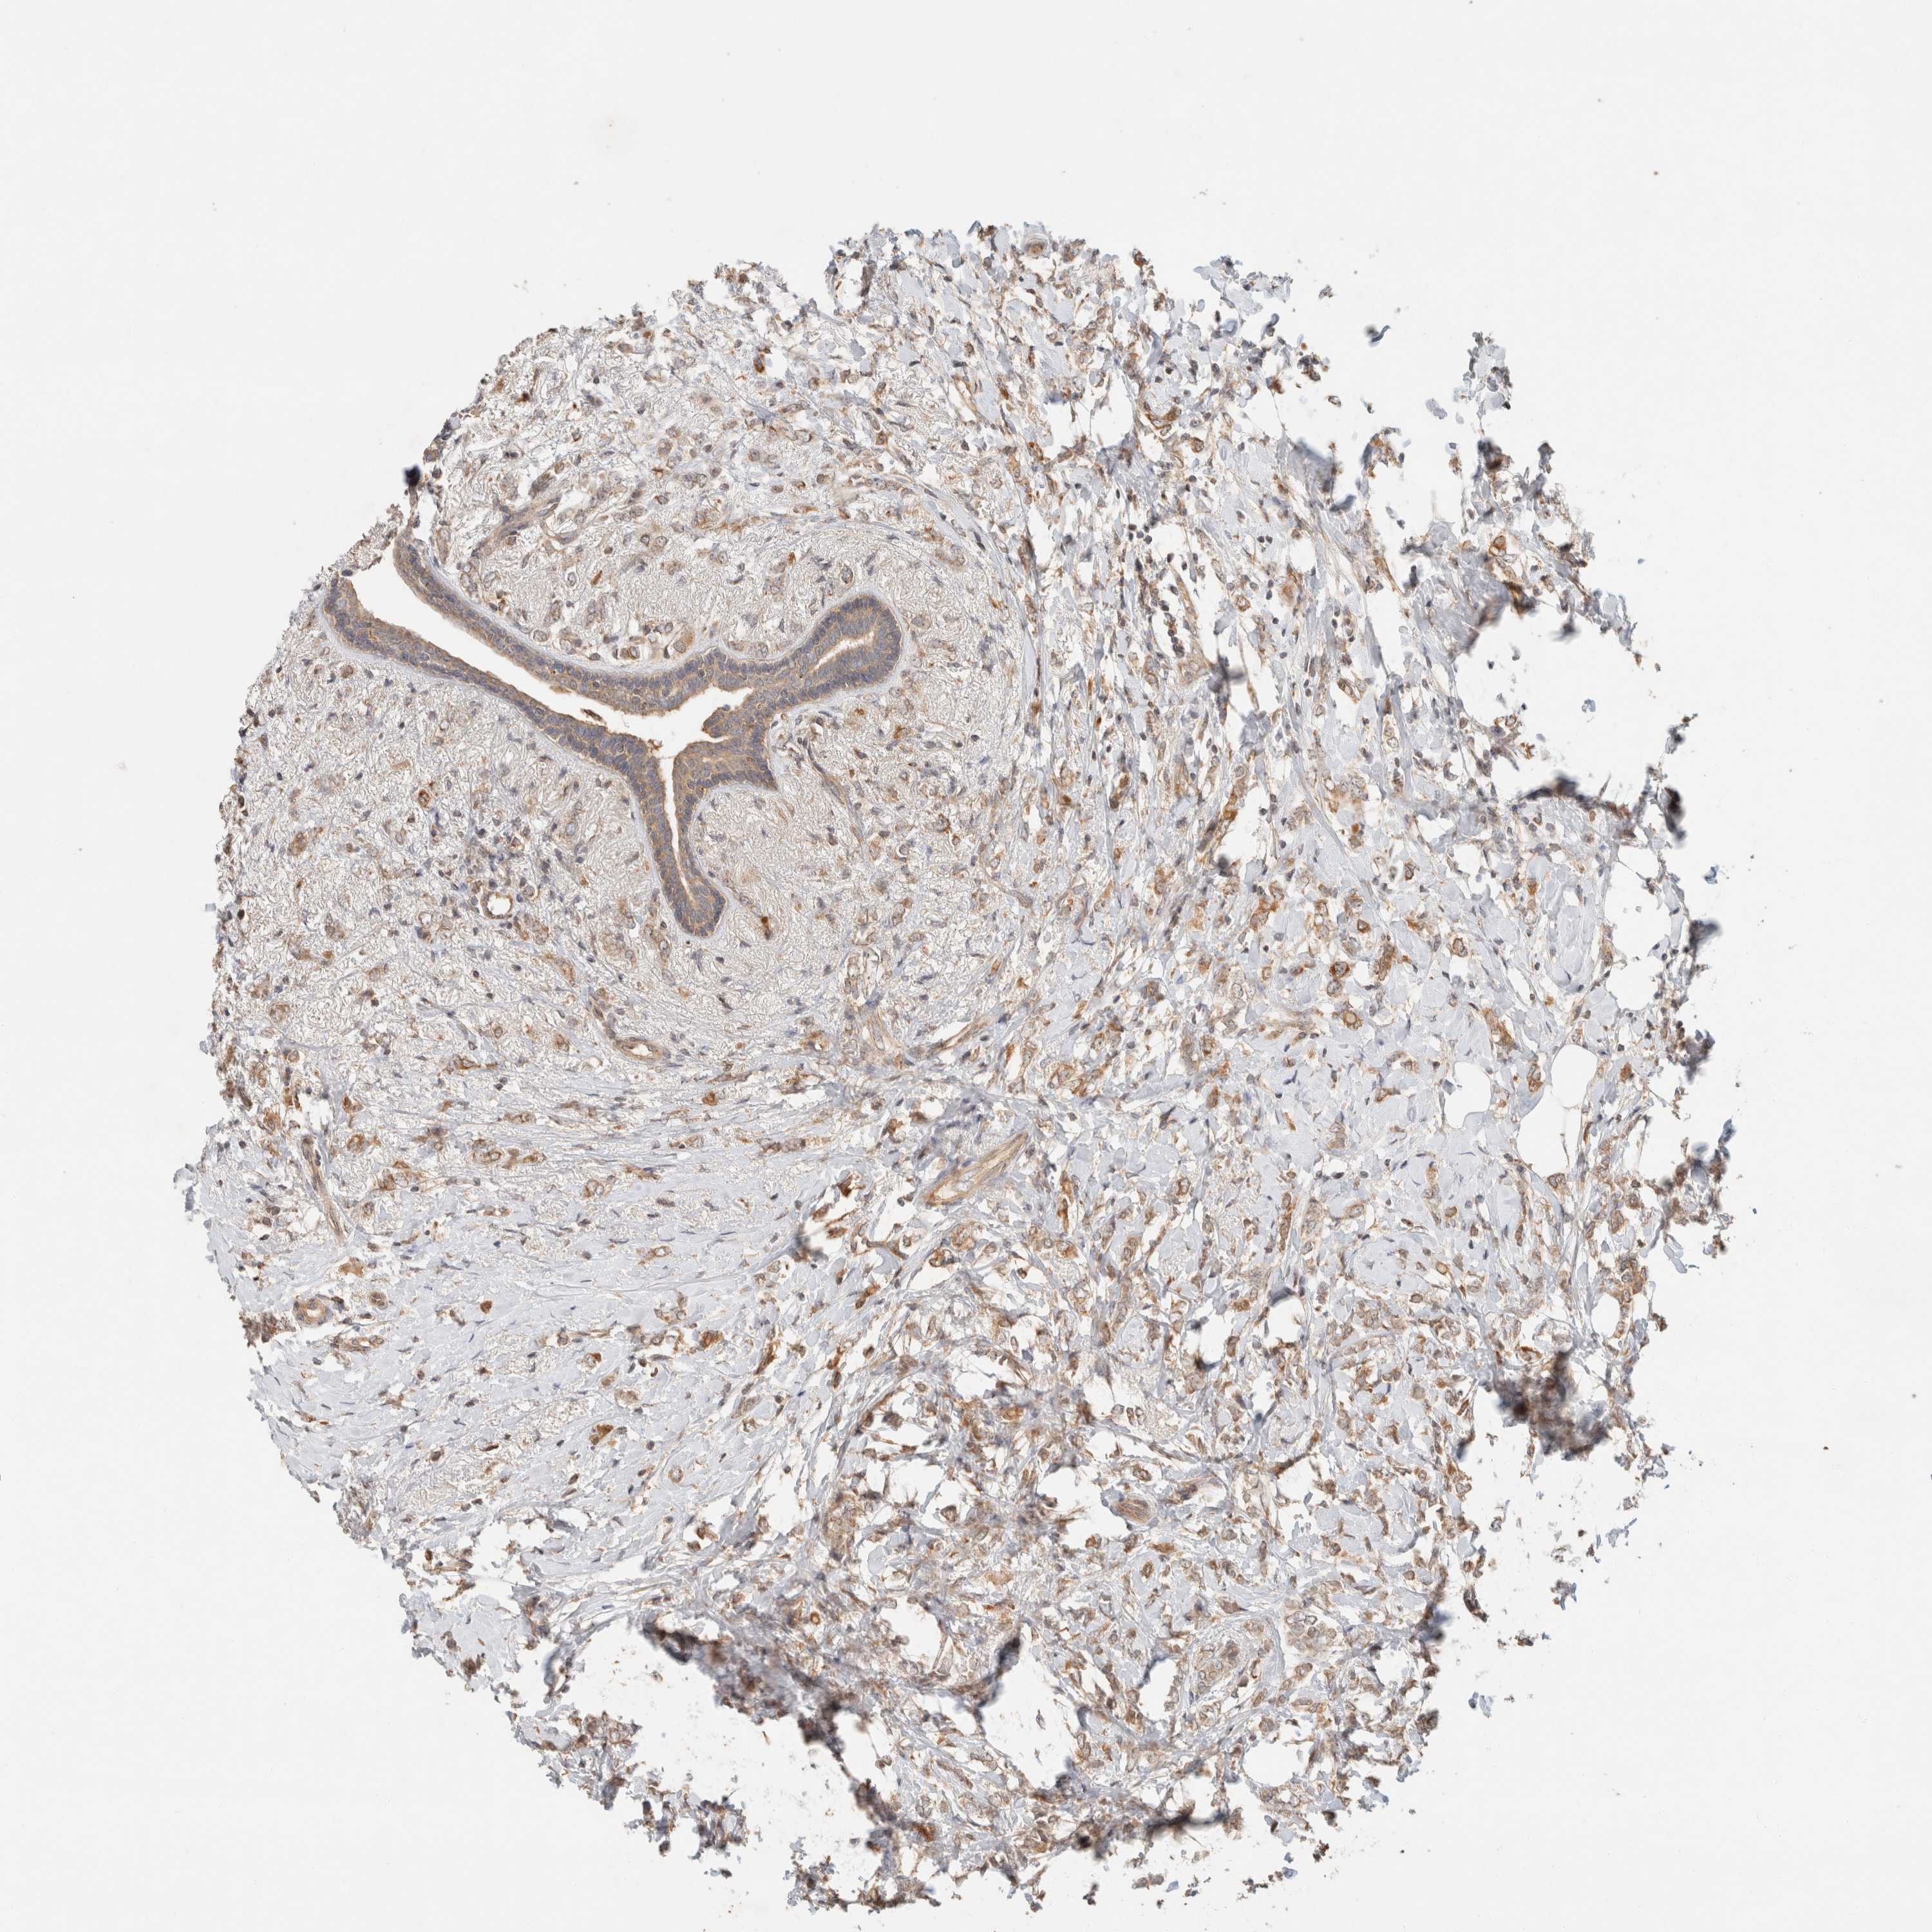

BRCA TCGA BRCA VALIDATION PROTEIN EXPRESSION

ANTIBODIES

AND

VALIDATION